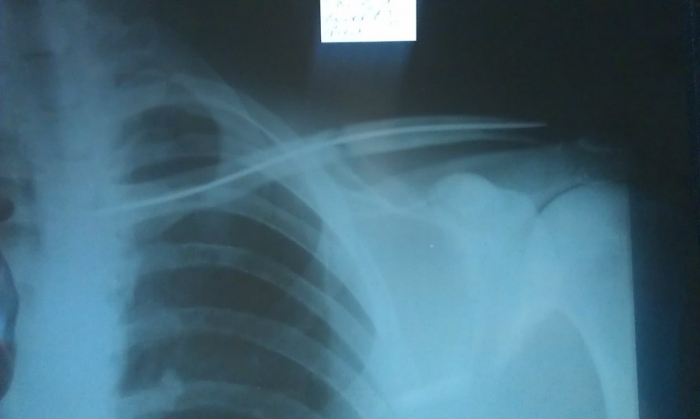

Перелом Ключицы Фото

Перелом Ключицы Фото 117 фото